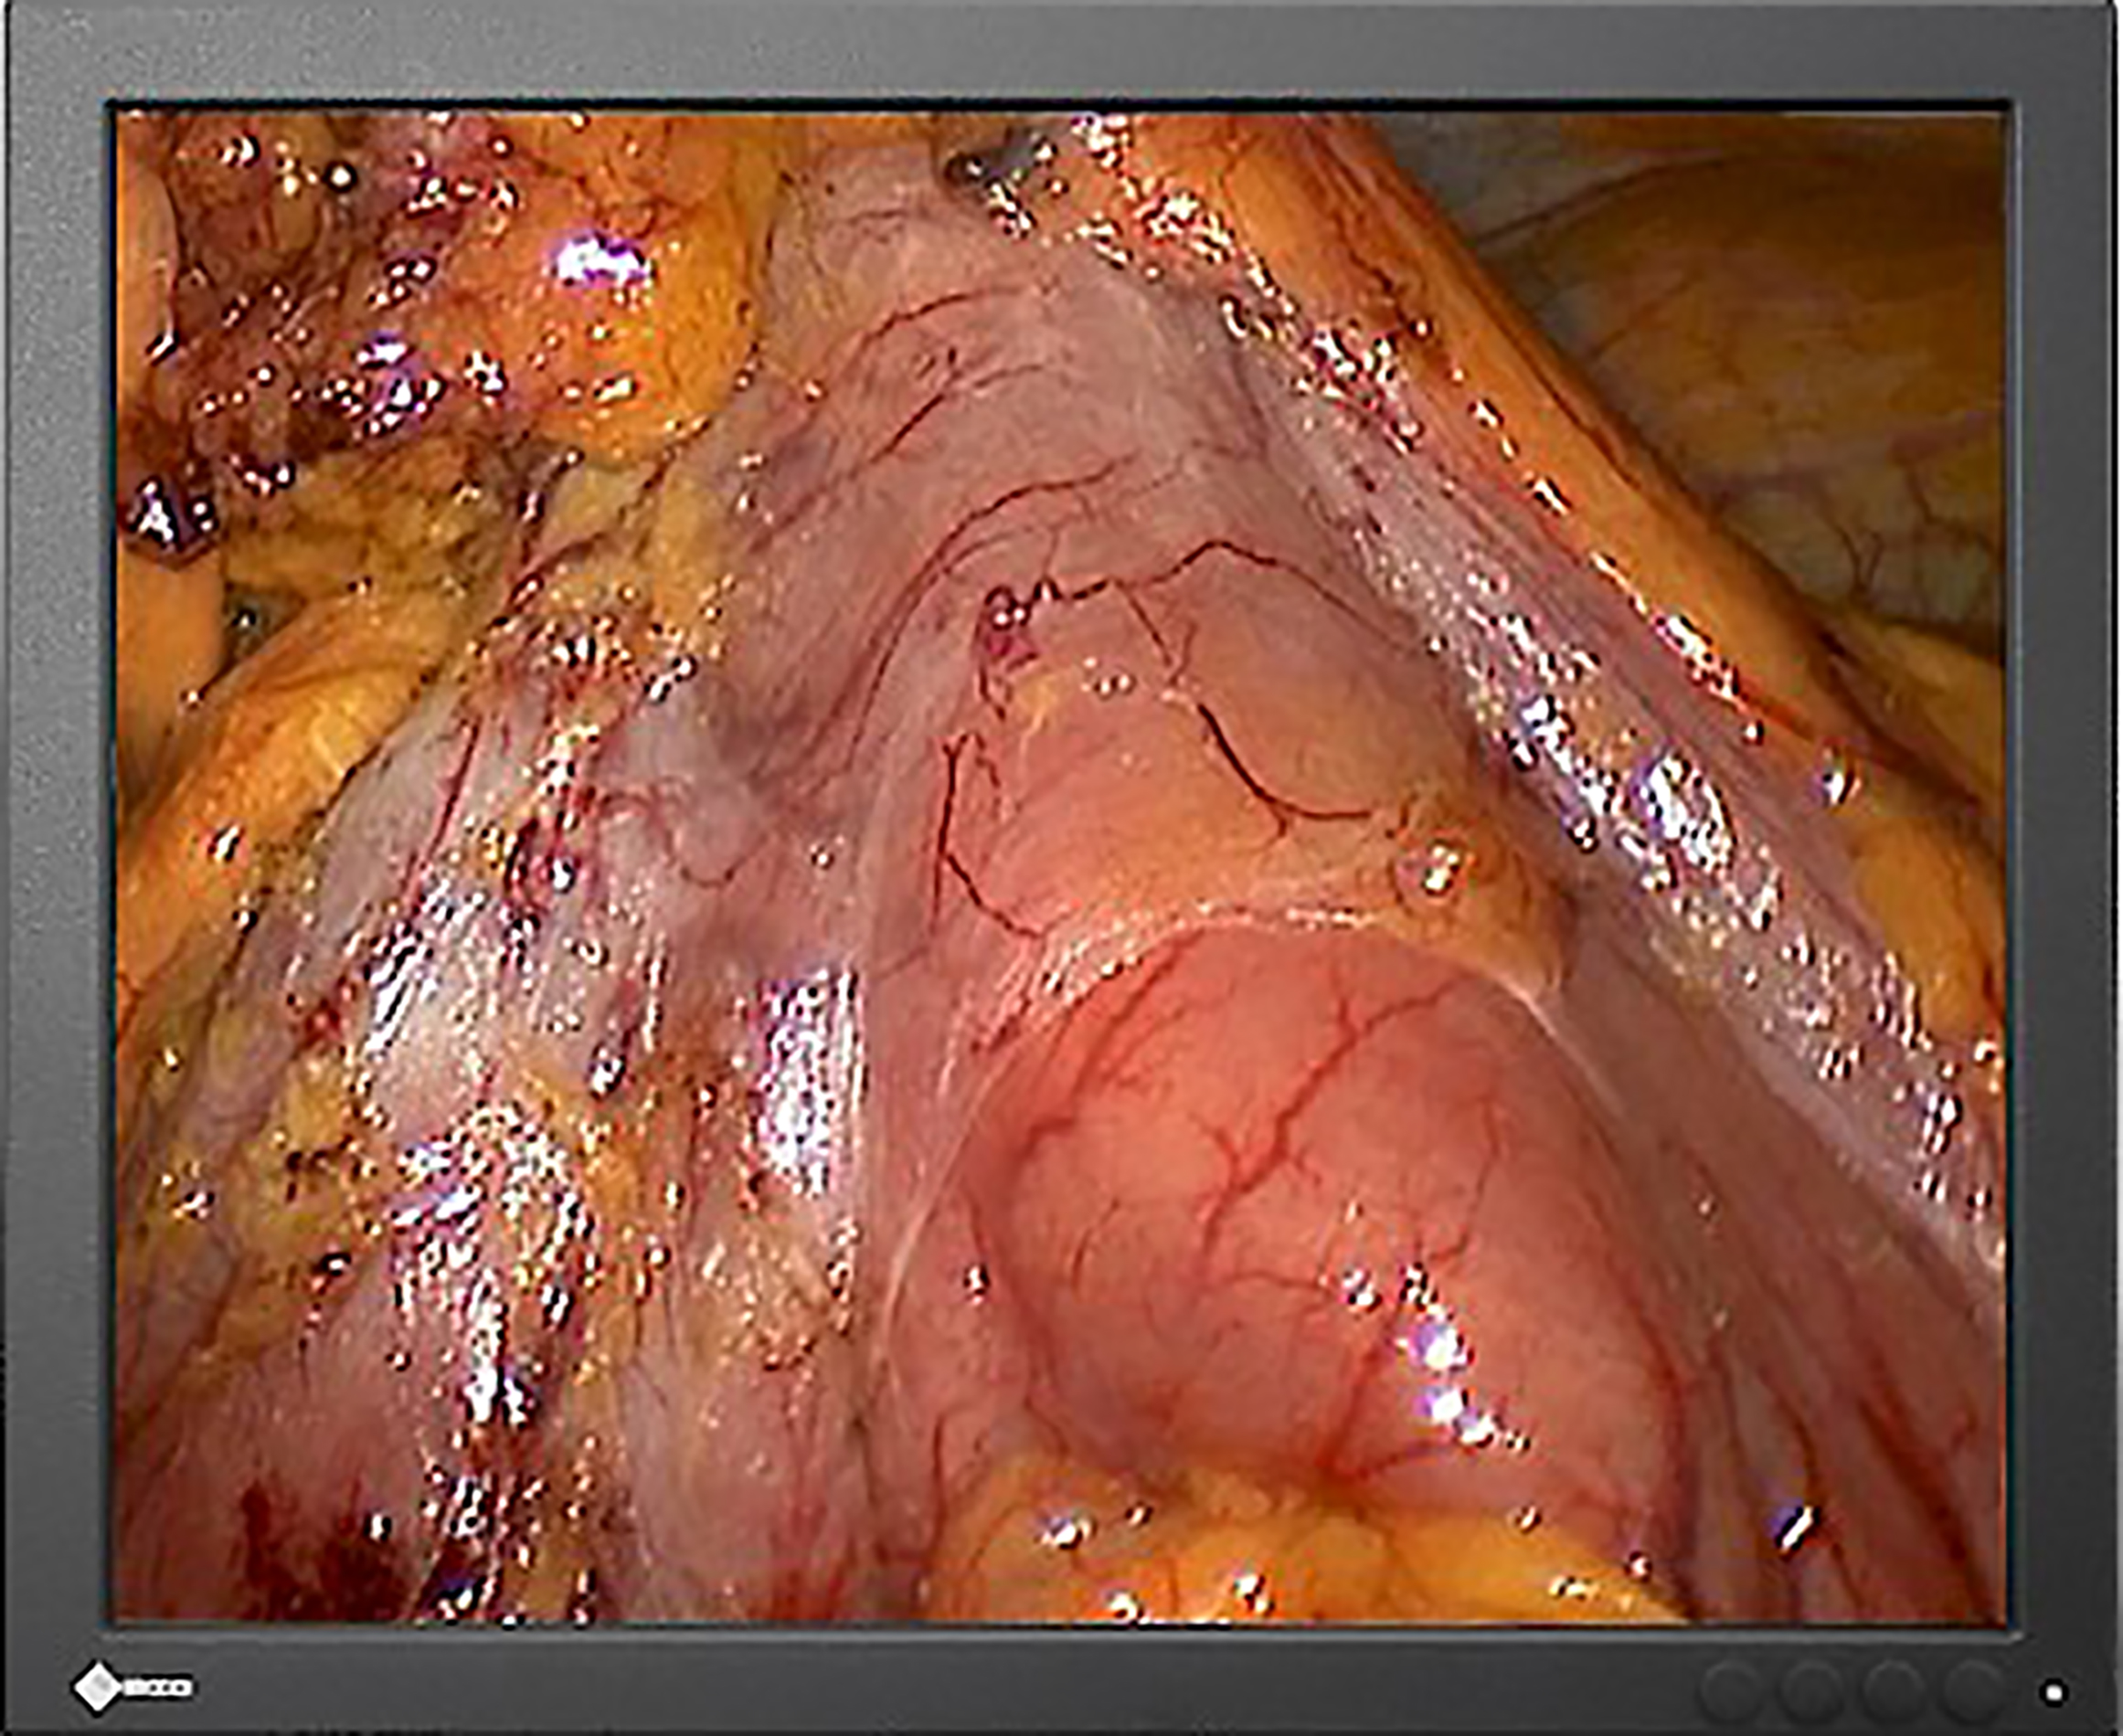

As the variety of different picture sources increases, state-of-the-art operating rooms are increasingly shifting from traditional X-ray film to displaying images on monitors. These images range from boom and endoscopy cameras to C-arms and Picture Archiving and Communication Systems (PACS). With EIZO’s surgical monitors, all images can be conveniently provided for clear decision-making and the highest diagnostic precision.